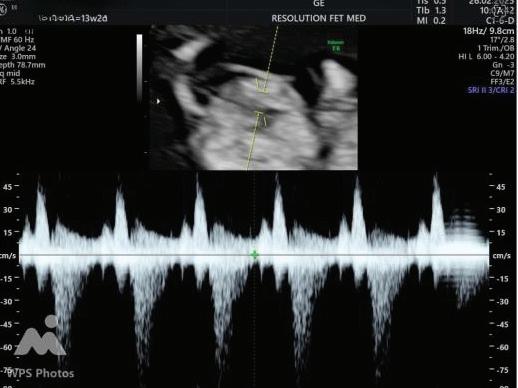

The first trimester— spanning from conception to 13+6 weeks—is no longer considered a “blind phase” of pregnancy. With the evolution of highresolution ultrasound, color Doppler and advanced biochemical screening, this period has transformed into a window of opportunity for early fetal evaluation, risk prediction and preventive strategies.

First-trimester fetal evaluation is not limited to dating the pregnancy or confirming viability—it is the foundation of predictive, preventive, and personalized obstetric care.

2. NUCHAL TRANSLUCENCY (NT) SCAN

• Done @11–13+6 weeks.

• CRL 45–84 mm.

• This is the cornerstone of first trimester screening.

1. NT is the sonographic appearance of subcutaneous accumulation of fluid behind the fetal neck, below the skin in the first trimester of pregnancy.

2. Measured in mid-saggital section only.

3. Measured between 11-14 weeks.

4. CRL between 45-84mm.

5. Magnified to include only head and upper thorax.

6. Fetus should be in neutral position.

7. Demostrate fetus separate from amnion.

8. Measurement should be ON to ON (cross bar of the callipers should be such that it’s hardly visible and merges with white line, not nuchal fluid).

During the scan more than one measurement should be taken and maximum value should be considered.

➢ In fetal cardiology, a large retrospective screening of 77,396 fetuses at 11–13+6 weeks demonstrated a detection rate of ~70.5 % for congenital heart disease (CHD) using a standardised firsttrimester cardiac scanning strategy.2

➢ The prospective study “Fetal Advanced Neurosonography in the First Trimester of Pregnancy” evaluated 92 fetuses (CRL 60–82 mm) and found that an extended first-trimester CNS ultrasound protocol was feasible in 93.5% of cases, with excellent intra- and interobserver concordance and only 3 extra minutes